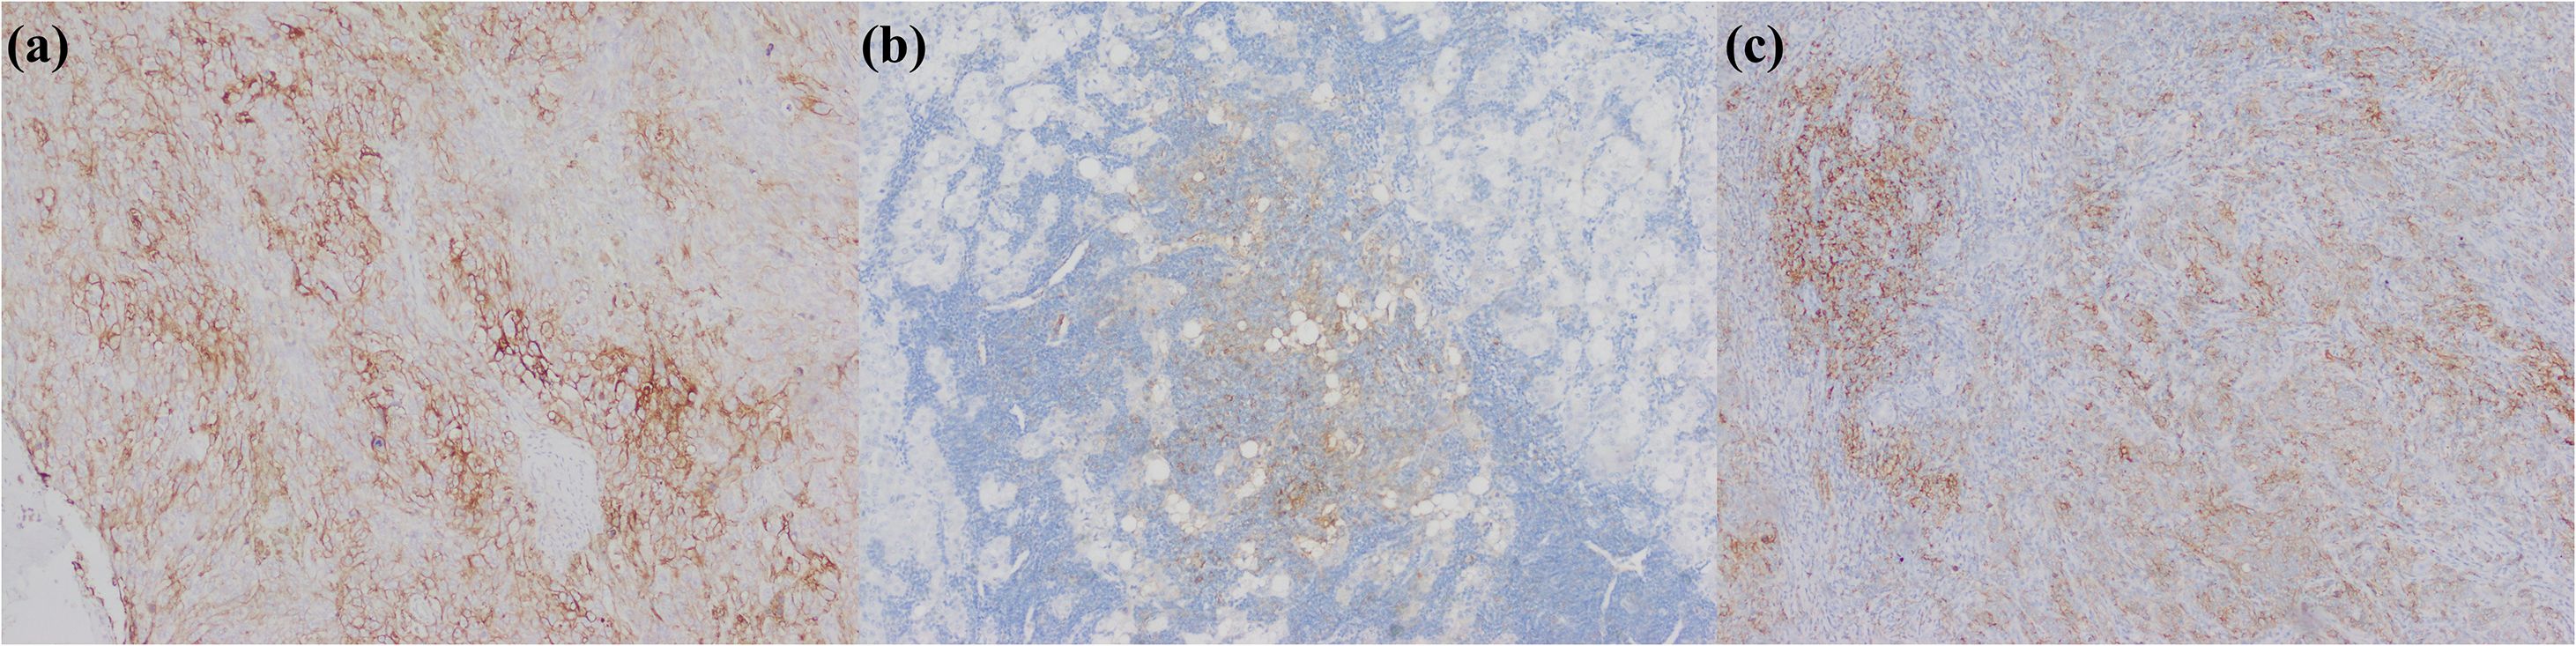

3.13 PD-L1 high expression

PD-L1 is notably expressed across tumor-associated cell populations, including neoplastic cells, stromal components, and myeloid lineages (Figure 11). Through dual ligand interactions with programmed death-1 receptors on T cells and CD80 co-stimulatory molecules on antigen-presenting cells, PD-L1 inhibits T cell proliferation, cytokine production, and cytolytic activity driving T cells toward a dysfunctional exhausted state (266). Although PD-L1 inhibitor Durvalumab has been approved for primary preferred treatment of biliary tract cancer, the connection between elevated PD-L1 expression and the therapeutic outcome of immunotherapy for iCCA remains uncertain but this relationship warrants attention. A study manifested that PD-L1 expression in biliary tract cancer could serve as a potential predictor for the therapeutic efficacy of Pembrolizumab. The objective response rate and disease control rate were higher in the high PD-L1 expression group [tumor-positive score (TPS) ≥ 50%] (267). In a single-arm phase II clinical trial of Camrelizumab combined with Gemcitabine and Oxaliplatin for the treatment of patients with advanced biliary tract cancer, the objective response rate of patients with PD-L1 TPS ≥ 1% was 80.0%, outperforming that of 53.8% of patients with PD-L1 TPS < 1% (268). A meta-analysis encompassing 30 studies investigated the predictive value of PD-L1 expression for the response to immunotherapy in biliary tract cancer and suggested that there was no significant distinction in the objective response rate and disease control rate between PD-L1+ and PD-L1- patients. Nevertheless, the progression-free survival and overall survival were enhanced in the former group. Within the included studies, the determination of PD-L1 positivity was mainly based on TPS ≥ 1% or combined positive score (CPS) ≥ 1 (269). Another meta-analysis incorporating 10 studies revealed that high PD-L1 expression was positively correlated with poorer overall survival and recurrence-free survival in iCCA (270). Hence, it is rationally supposed that although the prognosis of iCCA with high PD-L1 expression is unfavorable, immunotherapy may improve the prognosis of this subgroup. There were some proposed interpretation standards and validated clones for PD-L1 immunohistochemistry in recent years (271–273), which are used to assess PD-L1 evaluation in iCCA.

Figure 11. iCCA with heterogeneous PD-L1 expression. (a) PD-L1 is positively expressed in tumor cells; (b) PD-L1 is positively expressed in immunocytes; (c) PD-L1 is positively expressed in tumor cells and immunocytes.